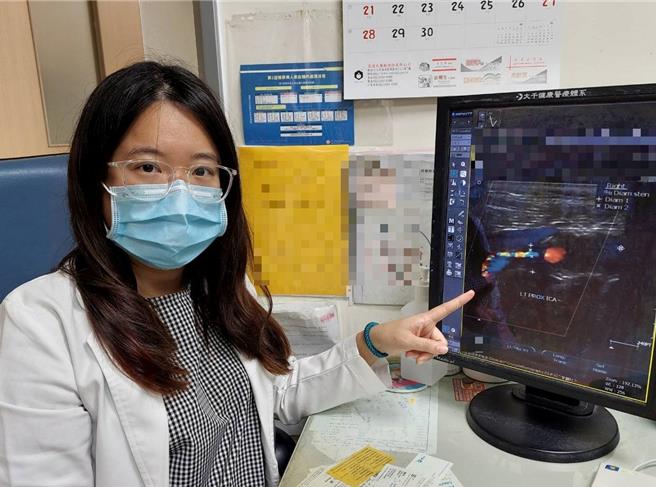

大千綜合醫院神經內科醫師李亭儀表示,中風可分為大血管病變、小血管病變、心因性血栓,其中最嚴重的是大血管病變,影響的腦區範圍最大,造成的殘障失能最嚴重、死亡率也高,而最常見的就是頸動脈粥狀動脈硬化。由於頸動脈供應大約2/3的半側大腦,當有高血壓、高血脂、高血糖、抽菸等危險因子時,就容易造成粥狀動脈硬化,隨著時間越來越嚴重,則會演變成頸動脈狹窄、甚至阻塞。

李亭儀解說,在頸動脈完全阻塞之前,常出現下列症狀:不明原因的昏厥、手腳無力發麻(尤其是半側的症狀)、暈眩、大舌頭等。當頸動脈阻塞較嚴重時,會引起半側大腦嚴重梗塞,還可能造成半側癱瘓、臥床等後遺症,甚至危及性命。如能在頸動脈尚未完全栓塞前,利用頸動脈超音波、電腦斷層、核磁共振、血管攝影等方法檢測出,在符合條件下,可進行頸動脈支架置放術,把狹窄的頸動脈撐開,增加腦部灌流,就可解決潛在的中風危機。